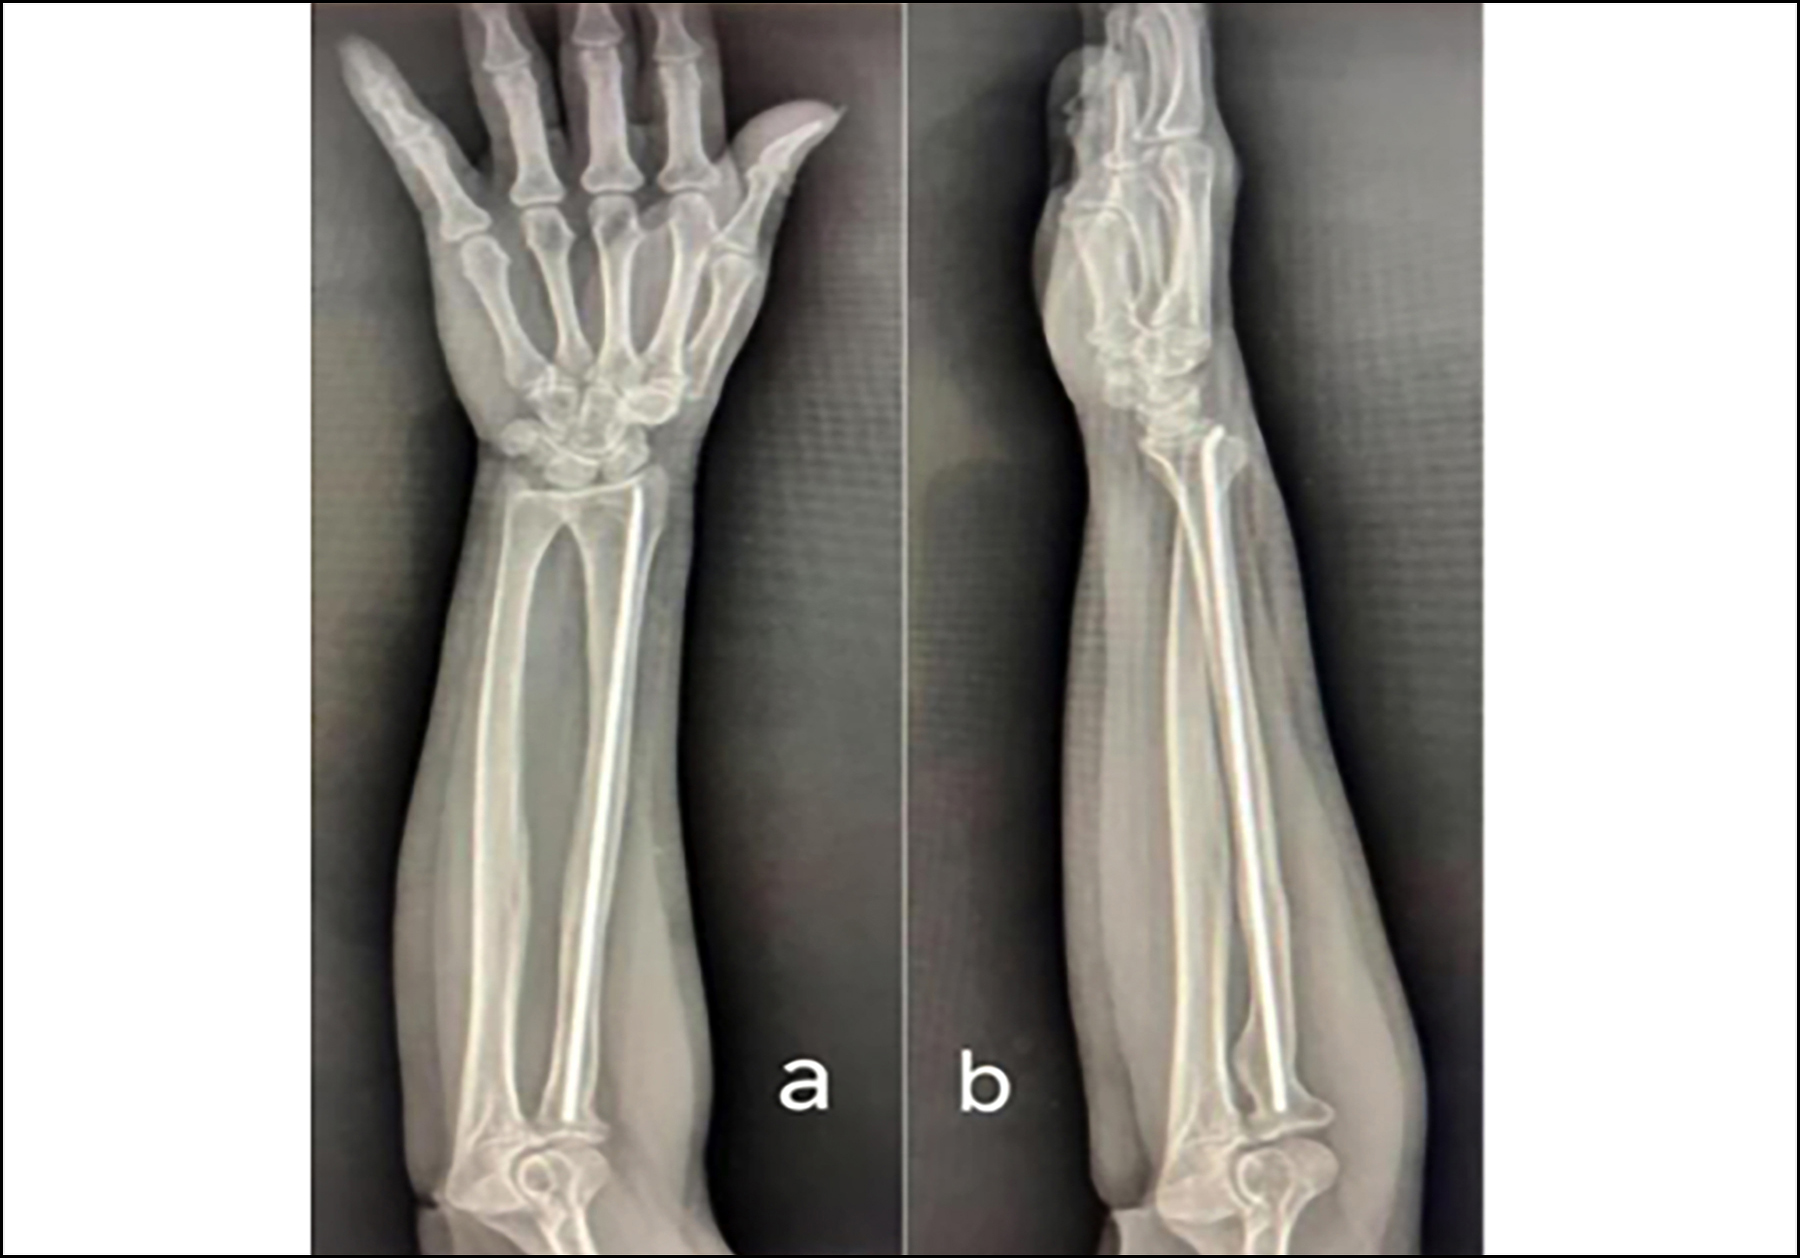

The patient was admitted with a diagnosis of ruptured right EPL tendon following surgical repair of a radial fracture. Preoperative imaging showed the intramedullary hardware remained securely positioned, with visible callus formation bridging the fracture site. However, a faint fracture line was still visible on scans, indicating incomplete healing. Ultrasound imaging definitively showed a full-thickness tear of the EPL tendon.

Figure 2: Radiographic union of the radial shaft fracture with bridging callus  across  three  cortices.

At twelve months post-revision surgery, imaging confirmed successful healing of the radial shaft fracture with callus bridging across three cortical surfaces, indicating bony union (Figure 2). The patient regained complete thumb extension strength (MRC grade 5), and dynamic ultrasound verified proper tendon integrity. Wrist mobility showed near-normal function, with 130° of flexion-extension, only 10° less than the unaffected side (140°). Forearm rotation reached 160° versus 170°contralaterally during combined pronation and supination movements. With a QuickDASH score of 12, the patient demonstrated outstanding functional outcomes, nearing full recovery (Figure 3).